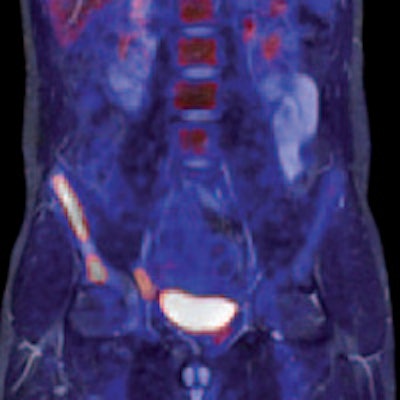

Left: PET tracer uptake in the liver can be combined with the time-varying enhancement of dynamic MR scans to visualize hepatic tumor characteristics. Right: MR and PET come together to support tumor staging. In this case, high-resolution MR provides a clear image of the pathology within the pelvic structure, while PET displays the hypermetabolism component of the lesion. Images courtesy of Siemens.Drzezga believes that combining the two modalities offers a number of clinical advantages, not least in eliminating the need for separate diagnostic examinations. Furthermore, the exact anatomical registration of structural and functional/molecular information may improve allocation of suspect findings and improve image quality, for example by motion correction of regions of the body that do not remain rigid during examination. The Munich team will also be exploring how the performance of PET/MR compares with that of PET/CT. There is some evidence that the superior soft-tissue contrast achievable with the newer system will offer significant benefits, even before physicians consider the safety issues involved with any radiation-based imaging technology such as PET/CT, Drzezga suggested.

Left: To improve the precision of spatial registration, the Biograph mMR system collects MR and PET data simultaneously from a single frame of reference. The result is a combined MR and PET scan acquired at the same point in time and reflecting the same point in the physiologic processes such as respiration. Right: The benefits of MRI in the study of neurological diseases are well-known and established, and it can lead to a better understanding of neurological pathologies. Images courtesy of Siemens.Philips has been working on its latest MR technology for almost as long as the search for a practical PET/MR hybrid. After an eight-year development project, the company is promoting its Ingenia 1.5- and 3-tesla systems, which it describes as the world's first digital broadband MR unit. This incorporates dStream architecture, which digitizes the signal directly in the coil. Vendors have been looking for ways to shorten the analogue part of the signal processing pathway because this offers the potential for reducing signal loss and noise. The Philips approach goes further by digitizing the signal within the coil itself and transporting it via a fiber-optic cable to the acquisition electronics contained in the scanner cabinet, explained Maurits Wolleswinkel, global lead for MR marketing.